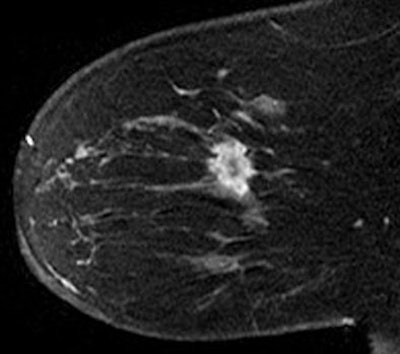

| Contrast-enhanced T1-weighted sagittal image in 62-year-old woman shows 24-mm mass with morphologic features common to malignant masses in this study: large size, irregular shape, irregular margins, and heterogeneous enhancement. |